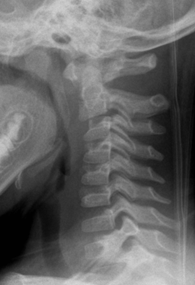

2. Pseudosubluxation of C2

Physiological anterior displacement of C2 on C3 is commonly seen in children, usually <7 years of age, less commonly in older children. It is most commonly seen at C2 on C3, but may less often be seen at C3 on C4. This finding is more pronounced in flexion and can present confusion in the presence of traumatic cervical injury .2 Utilization of Swischuk’s line is useful in differentiating pathological anterior cervical spine displacement from physiological displacement. This line is drawn from the anterior aspect of posterior arch of C1 to anterior aspect of posterior arch of C3 3 and should measure less than 2-mm. A measurement of greater than 2-mm indicates true subluxation. It is important to note that this line should only be used in the absence of other signs of instability and in the absence of prevertebral soft tissue swelling.

Figure 3: a) Pseudosubluxation in a 5-year-old. b) Zoomed in view to demonstrate Swischuk’s line. Case courtesy of Radiopaedia.